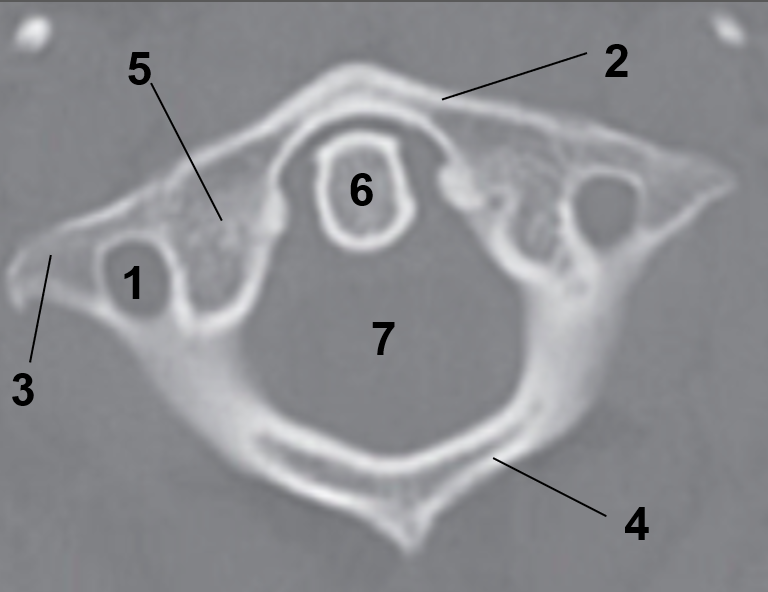

1?

Hard Palate

2?

Maxillary Bone

3?

Mandibular Rami

4?

Dens

5?

Transverse Foramen C1

6?

Spinal Cord

7?

Auricle

8?

Atlas